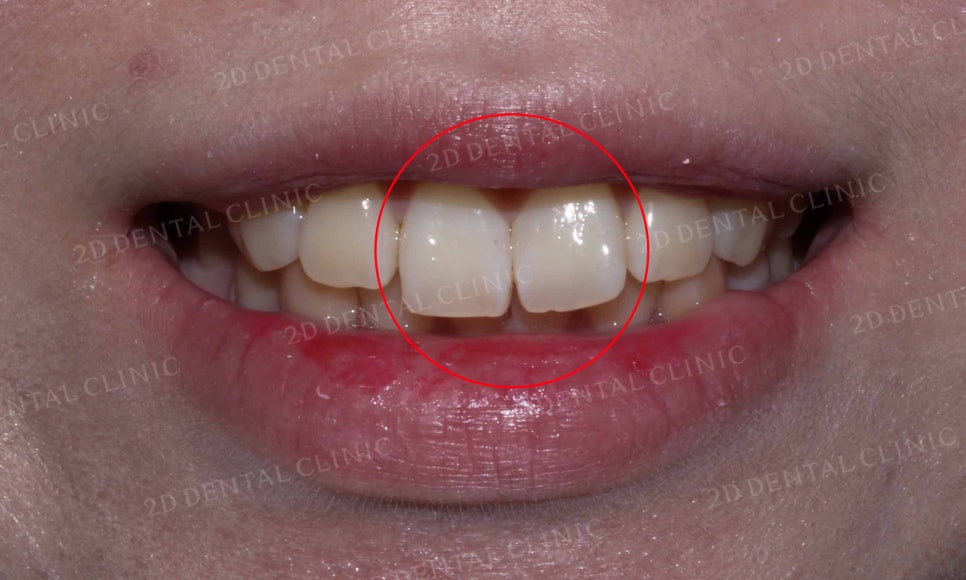

"토끼앞니 교정(Before)"

토끼앞니 2D교정 전

2D치과(투디치과)

토끼앞니 교정 전 입술의 모습을 보시면

앞니가 입술 방향으로 뻐드러져 있기 때문에

입술이 튀어나온 듯한 느낌이 듭니다.

미소를 지었을 때 보이는 앞니의 모습도

토끼처럼 앞니 2개가 눈에 띄는 모습인데요,

윗니와 아랫니의 중심도 잘 맞지 않아

앞니가 옆으로 삐뚤어진 모습입니다.